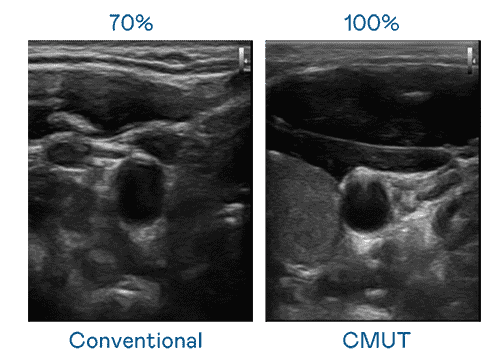

CMUT 技术是一种用电容式微机电元件来产生超音波讯号的技术。。与传统 PZT 压电式技术相比,,CMUT 频宽增加 30%,,,更宽频的超音波讯号让影像解析度大幅提升,,是实现高影像品质医疗超音波扫描、、、促进精准医疗发展的关键技术。。。

大频宽带来超清晰影像

超音波影像的解析度高低,,首先取决于探头能发出的讯号频宽。。万利 CMUT 可提供高清晰的超音波讯号,,,,提供高频宽、、高灵敏度、、、影像纹理细节更高的超音波影像,,,,协助医护人员缩短影像判读时间及利用精准的医疗影像进行诊断。。。